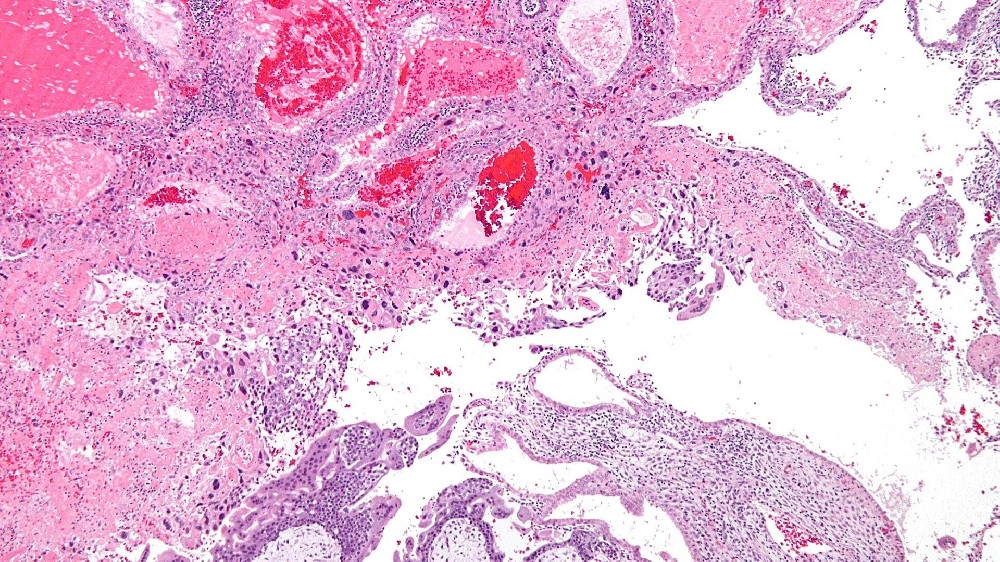

妊娠滋養細胞疾病 (Gestational Trophoblastic Disease, GTD) 是一種罕見的腫瘤,源自胎盤組織,特別是滋養細胞。滋養層細胞通常在懷孕期間發育成胎盤,幫助滋養胚胎。然而,滋養母細胞的異常可導致不受控制的生長,形成腫瘤或囊腫,並啟動妊娠滋養細胞疾病 (GTD)。

在全球範圍內,每 1,000 名孕婦中約有 1 例發生妊娠滋養細胞疾病 (GTD),其亞型各異,包括水滴形痣 (包括完全性和部分性)、浸润性痣、絨毛膜癌和胎盤部位滋養細胞瘤。然而,地區性的差異很普遍,特別是在香港和亞洲其他地區,GTD的發生率較高。

雖然與 GTD 有明顯關聯的特定遺傳基因非常罕見,但基因組研究突顯了與 GTD 亞型相關的染色體異常。例如,完全水滴形痣通常是由父系基因組重複所造成 (46XX 核型,完全源自父系)。相反地,部分水滴形痣通常會顯示三倍核型 (69 條染色體),混合母源與父源。